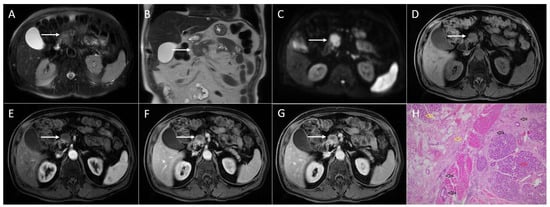

3.3. Intrapancreatic Accessory Spleen